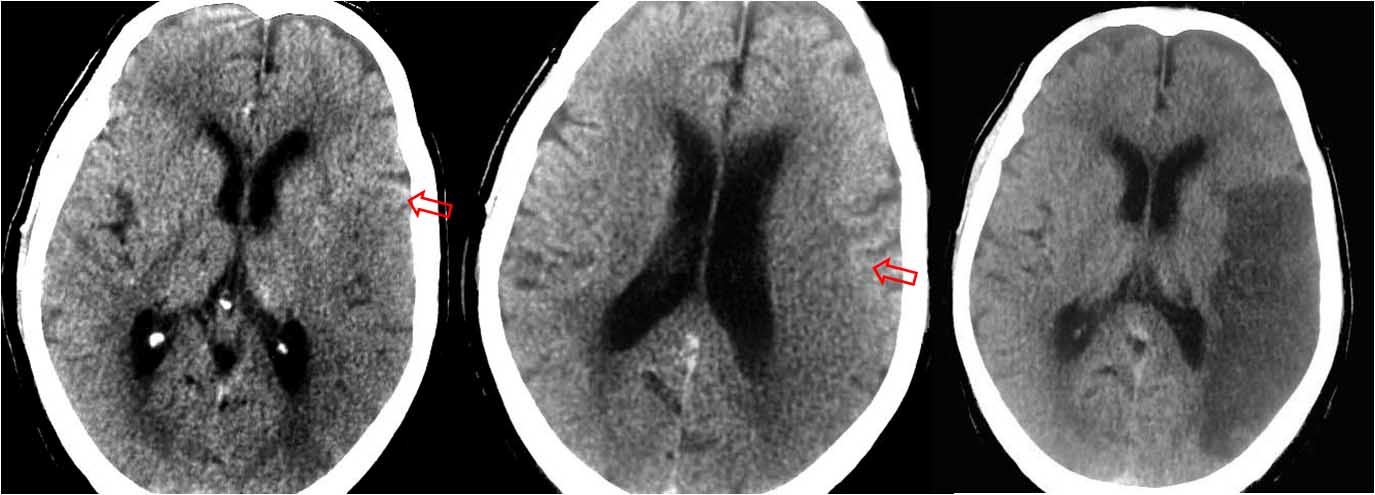

SIGNO DEL OSCURECIMIENTO DEL NÚCLEO LENTICULAR

Signo precoz de infarto isquémico de la arteria cerebral media, visto en TC y descrito por Tamura en 1988. Consiste en la disminución de la densidad del núcleo lenticular -en comparación con la contralateral-, producida por el edema subsecuente al infarto, que puede verse en las primeras horas del comienzo del accidente isquémico, en ocasiones hasta tan solo una hora después del inicio de la isquemia.

El signo tiene una buena correlación con el infarto del territorio profundo de la arteria cerebral media, con un valor predictivo positivo del 99 % y un valor predictivo negativo del 98 %.

Otro ejemplo del signo a la izquierda) afectando al lenticular derecho, y la evolución tomográfica a la derecha).